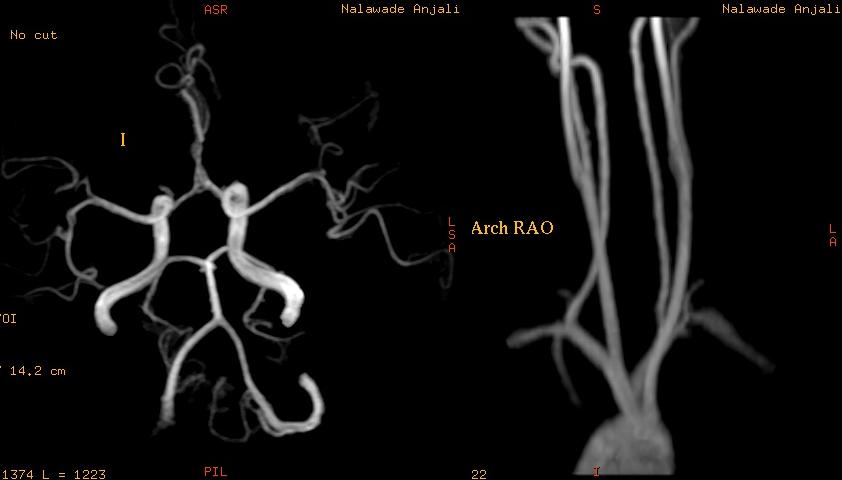

State Of The Art Imaging In Autoimmune Cerebral Vasculitis

State of the Art Imaging in Autoimmune Cerebral Vasculitis Pia C. Sundgren, M.D. Ph.D1 and Attwood J, McCune J, Maly P: Value of MRI of the brain in patients with systemic lupus erythematosus and neurologic with neuropsychiatric systemic lupus erythematosus with new acute ... Retrieve Doc

Magnetic Resonance Imaging And Magnetic Resonance Angiography ...

Magnetic Resonance Imaging; Central Nervous Sytem Diseases Archive of Oncology 2001,9(1) MR imaging of systemic lupus ery-thematosus involving the brain. AJNR 1985;6:197-201. 4. Greenan UJ, Grossman RI, Goldberg HI. Cerebral vasculitis: MR imaging and angiographic correlation. Radiology 1992 ... Access Content

Angiography Of Medium And Large Vessel Vasculitis

Systemic lupus erythematosus Nolla JM, et al. Giant cell arteritis and polymyalgia rheumatica: usefulness of vascular magnetic resonance imaging in the diagnosis of aortitis. Rheumatology Large-vessel vasculitis. Arthritis and Rheumatism ... Access Doc